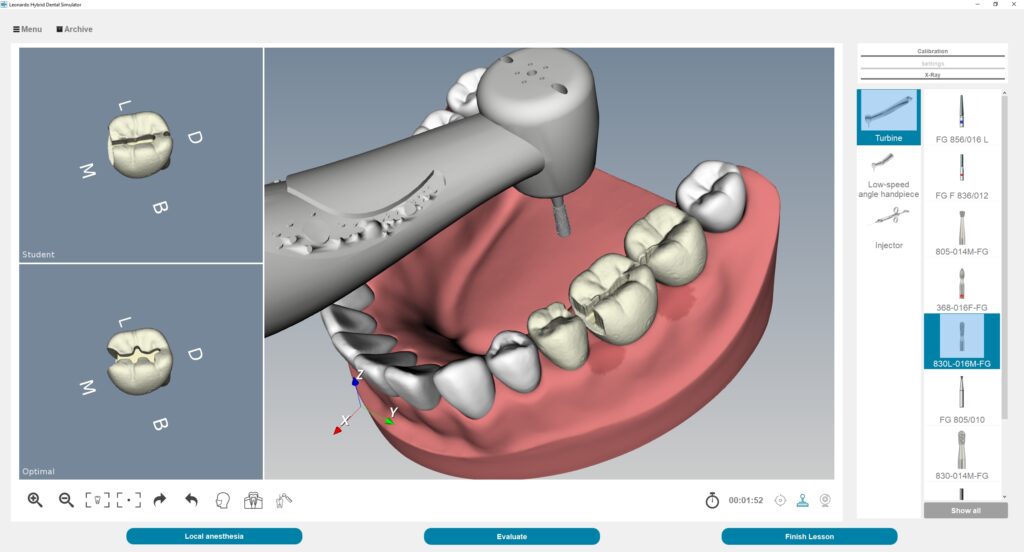

The Global Dental Simulator Industry is poised for a remarkable upswing, with projections forecasting a staggering growth trajectory. According to a recent analysis, the market is expected to reach an impressive US$780.5 million by 2033, reflecting a robust Compound Annual Growth Rate (CAGR) of 7.8% from 2023. This significant increase highlights the growing adoption of dental simulators for dental education and training purposes.

The increasing need for simulation-based training in dentistry clinics is what is behind this exponential rise. Dental simulators, which offer a more affordable option to more conventional techniques utilizing cadavers and study models, are becoming essential instruments for dental teaching and training.

One of the pivotal factors fueling this growth is the increasing adoption of human-like texture dental simulators, equipped with haptic feedback responses. This trend is particularly pronounced in dental schools across developing countries, where awareness of advanced training methodologies is on the rise. The realistic simulation offered by these dental simulators not only enhances the learning experience but also contributes to substantial cost savings.

When compared to more expensive dental mannequins or working on real patients, dental simulators offer a more affordable training option. Simulators enable numerous students to practice at once, minimizing the need for one-on-one supervision and maximizing the use of available materials. Dental schools, training facilities, and practitioners find dental simulators to be an appealing option because of their affordability.

Modernization of Dental Education

For dental students, dental simulators offer a lifelike and engaging learning environment. There is an increasing need for cutting-edge training tools that help improve practical abilities as dentistry education progresses. By bridging the gap between academic knowledge and actual practice, dental simulators can enhance learning results. These factors positively stimulate the dental simulator industry.

Growing Attention to Patient Safety

In dentistry, patient safety comes first. Dental experts can practice different treatments with dental simulators without having to worry about hurting actual patients. They enable dentists to learn crucial decision-making abilities and improve patient safety by simulating difficult dental scenarios, crises, and problems. Dental simulators have prospects in the market due to the increased awareness of and emphasis on patient safety.

Growing Demand for Practical Training

Hand-eye coordination and accurate manual dexterity are needed for dental operations. For dental students and professionals to learn and hone these abilities, hands-on instruction is crucial. Dental simulators allow users to practice and refine their techniques in a controlled environment while delivering a realistic simulation of dental treatments.